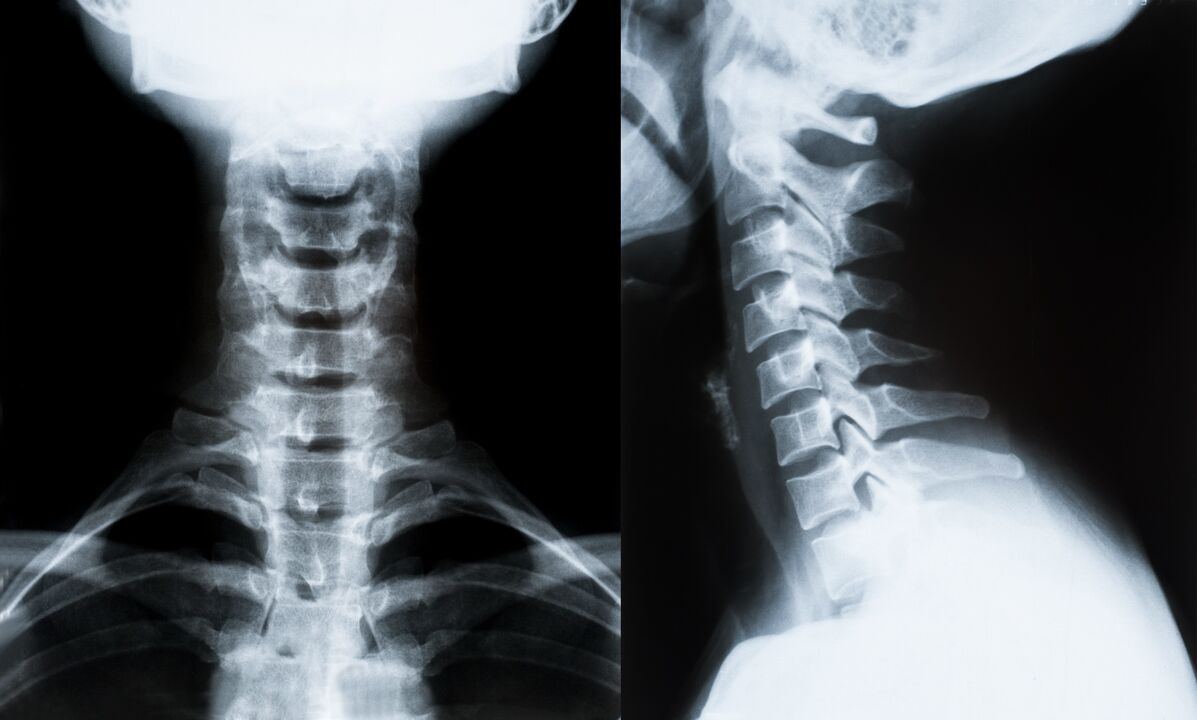

Principalele metode de diagnostic și determinarea ulterioară a tratamentului pentru osteocondroza coloanei cervicale:

- cu raze X. Cea mai puțin eficientă, dar tradițională metodă de diagnostic.

- Imagistica prin rezonanță magnetică este cea mai eficientă metodă de diagnostic. Cu acest tip de examinare a pacientului, toate structurile necesare sunt vizibile.

- Dacă trebuie măsurate modificări, se utilizează tomografia computerizată. Determină prezența herniilor și a altor lucruri.

- Ultima metodă este scanarea duplex cu ultrasunete. Această metodă de cercetare determină viteza fluxului sanguin în artere.

Este imposibil să determinați cu exactitate boala coloanei vertebrale acasă.